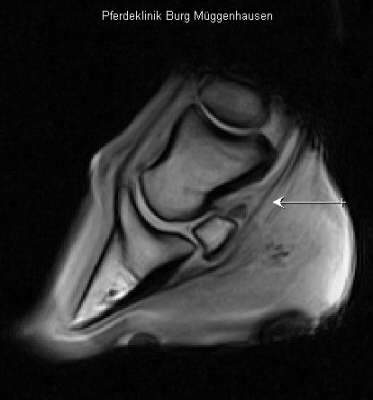

Im Bereich des Pfeiles deutlich weiß veränderte tiefe Beugesehne als Anzeichen eines gravierenden Schadens.